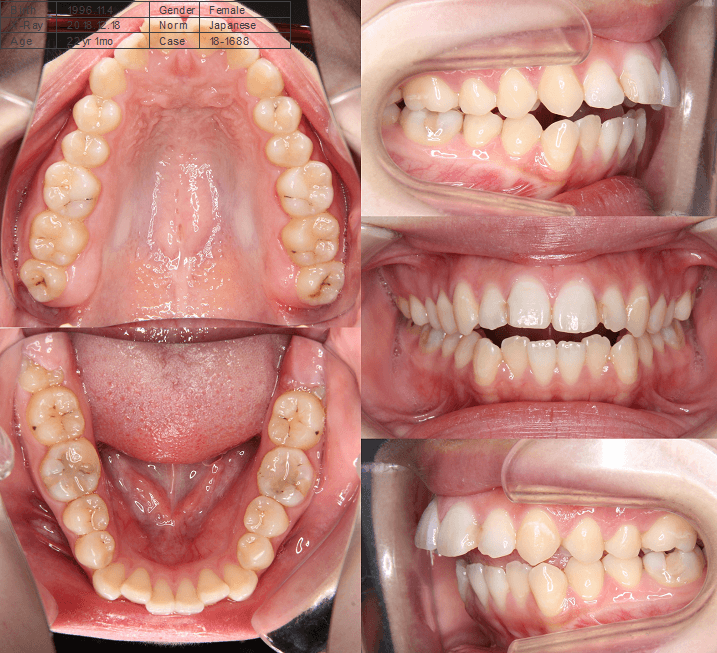

| 年齢・性別 | 15歳の女性 |

|---|---|

| 主訴 | 咬み合わせが逆であること(反対咬合)を気にされて来院された15歳7か月の女性。見た目や機能面の改善を希望されていました。 |

| 治療期間・回数 | 4年4ヶ月・28回 |

| 費用 | 900,000円 |